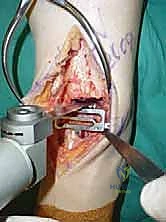

يقوم الدكتور هطيف بعمل شق طولي دقيق في الجزء الأمامي من الكاحل، طوله حوالي 10-15 سم. يتم تشريح الأنسجة بعناية فائقة للوصول إلى المفصل.

* الحماية العصبية الوعائية: هذه هي الخطوة الأكثر حرجاً. يتم تحديد الحزمة الوعائية العصبية (الشريان الظنبوبي الأمامي والعصب الشظوي العميق) وسحبها برفق شديد لحمايتها من أي ضرر جراحي.

3. إزالة النتوءات العظمية وتحضير المفصل (Debridement)

بمجرد كشف المفصل، يقوم الجراح بإزالة الغشاء الزلالي الملتهب والزوائد العظمية (Osteophytes) التي تعيق الحركة. هذه الخطوة ضرورية لاستعادة المعالم التشريحية الطبيعية قبل إجراء القطع العظمي.

4. وضع أدلة القطع (Jig Placement and Alignment)

تعتمد دقة الجراحة على المحاذاة الصحيحة. يتم استخدام أجهزة توجيه متطورة (Jigs) تثبت على عظمة الساق باستخدام دبابيس معدنية. يتم التحقق من صحة الزوايا والمحاور باستخدام جهاز الأشعة السينية المباشر داخل غرفة العمليات (C-arm Fluoroscopy). يضمن الدكتور هطيف أن يكون القطع موازياً للأرض تماماً عند وقوف المريض.